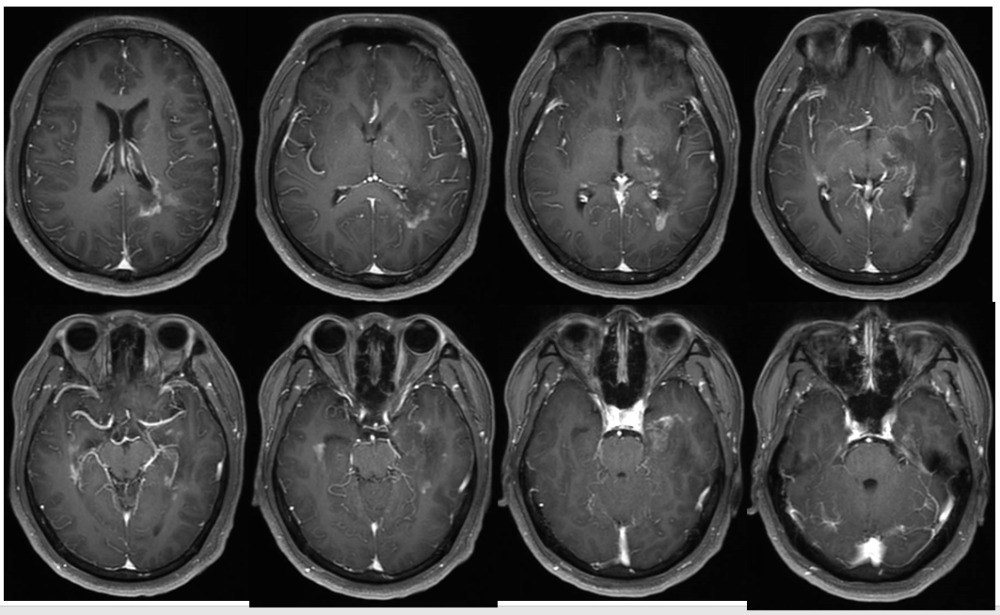

16张mri影像征,助你"征"服中枢神经系统脱髓鞘疾病丨实战读片

中枢神经系统脱髓鞘疾病ppt

脱髓鞘疾病腔隙性脑梗死与血管周围间隙的鉴别诊断